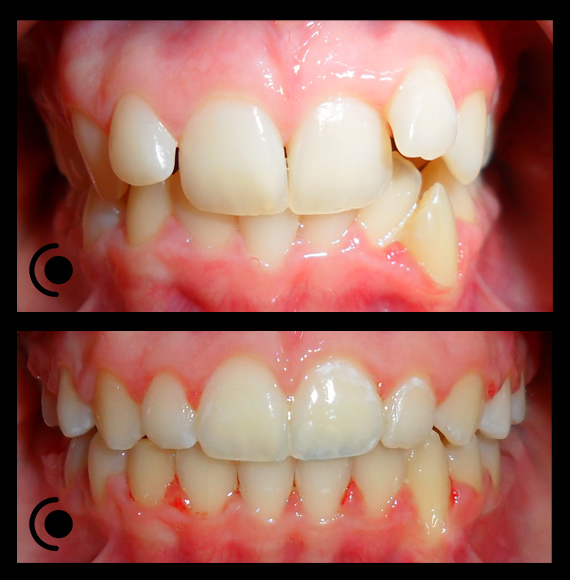

O našoj kvaliteti najbolje govore naši rezultati!

Centar za ortodonciju Petra Džapo